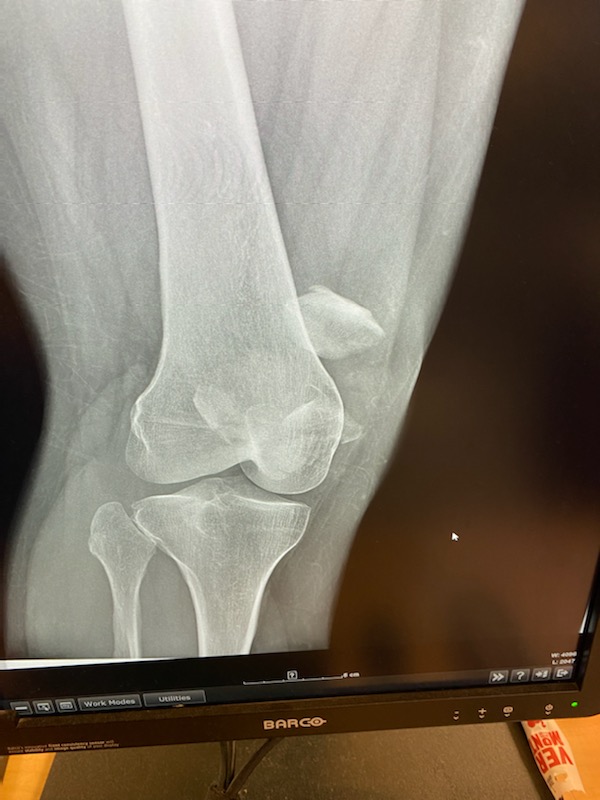

I slipped and fell, fracturing my patella into multiple pieces. I was placed into an immobilizer and sent home to find an orthopedic trauma surgeon. My aunt who is in the orthopedic industry, a friend who is a physical therapist/trainer and another orthopedic physician all highly recommended Dr. Nicholas Sama. Dr. Sama had me in his office literally the next day. He reviewed my records and imaging and explained my injury which was severe. He explained the possible treatments available and the all the risks associated. ORIF of the patella was to be my treatment. I was scheduled the following week at HSS Florida in West Palm Beach, which by the way is a fantastic facility. The procedure was again explained in detail and surgery commenced. Dr. Sama and his team worked meticulously at repairing my patella. Eleven screws and a mesh plate later, surgery was complete. I was placed in an immobilizer and was literally on my feet an hour after surgery. Two months post-op and I'm at 90% full mobility and all done without physical therapy! Dr. Sama literally is a godsend. He is an a amazing surgeon with fantastic bedside manner, which are attributes in the healthcare industry that are hard to find together!